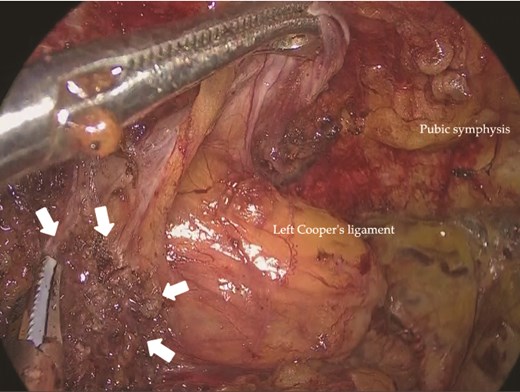

Under general anesthesia, a 12-mm camera port was inserted through the umbilicus, and two 5-mm ports were placed in the lower quadrants. Laparoscopic exploration revealed two mesh plugs on the left with fibrotic scarring and adhesions, which obscured the exact hernia orifice (Fig. 2). An incidental right direct hernia (M3) was also identified intraoperatively. Because severe adhesions were anticipated on the left, the operation was initiated on the right. A high peritoneal incision was initiated medial to the right anterior superior iliac spine (Fig. 3). The pseudosac was dissected while preserving the retropubic fascia, and the preperitoneal dissection was extended across the midline into the left side (Fig. 4). Approaching from the contralateral side allowed progressive entry into the adhesion-laden region through an unscarred plane, improving visualization and minimizing peritoneal injury.

Laparoscopic view of the left inguinal region showing two previously placed mesh plugs (arrows). No definite recurrent hernia orifice was identified. Dense adhesions were present around the plugs.

Intraoperative view of the right inguinal region before repair. A right indirect inguinal hernia with a defect measuring >30 mm was observed (arrows). A high peritoneal incision was made near the right anterior superior iliac spine.